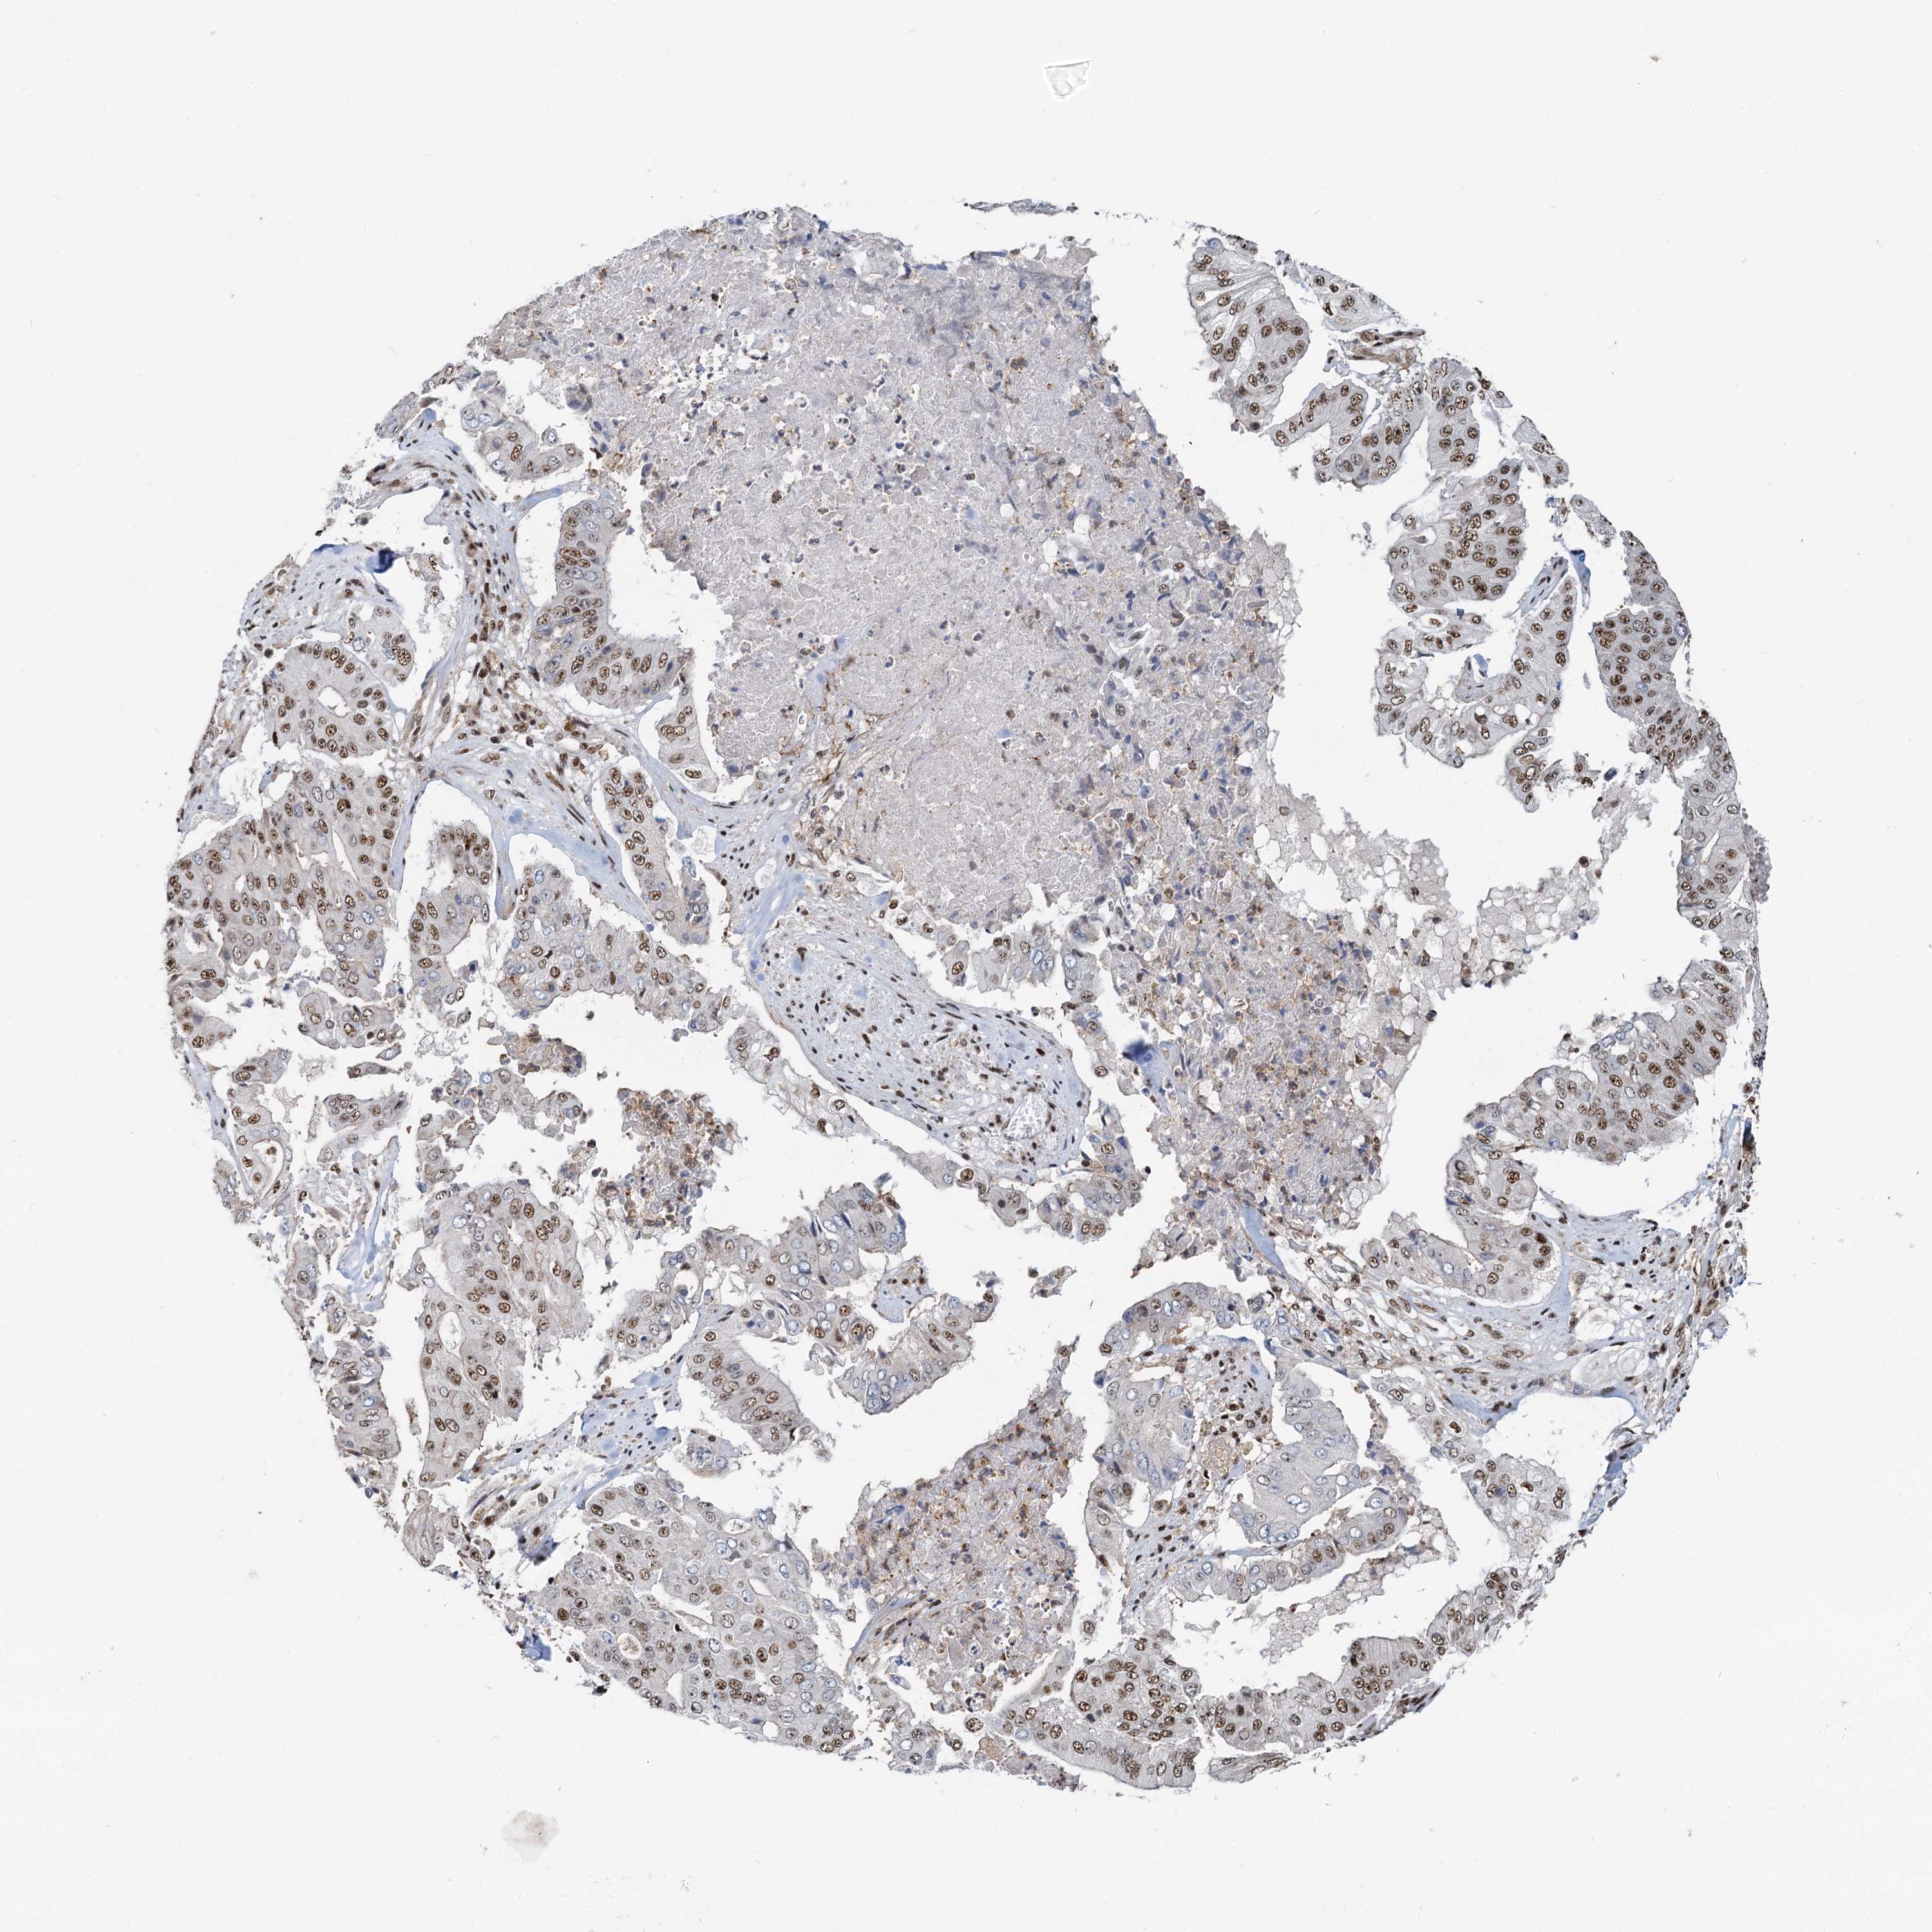

PANCREATIC CANCER - Protein expressioni

A mouse-over function shows sample information and annotation data. Click on an image to view it in a full screen mode. Samples can be filtered based on level of antibody staining by selecting one or several of the following categories: high, medium, low and not detected. The assay and annotation is described here.

Note that samples used for immunohistochemistry by the Human Protein Atlas do not correspond to samples in the TCGA dataset.

Antibody stainingi

Antibody staining in the annotated cell types in the current human tissue is reported as not detected, low, medium, or high, based on conventional immunohistochemistry profiling in selected tissues. This score is based on the combination of the staining intensity and fraction of stained cells.

Each image is clickable and will lead to virtual microscopy that enables deeper exploration of all samples and also displays staining intensity scores, fraction scores and subcellular localization as well as patient and tissue information for each sample.

Antibody HPA040252

Staining

High

Medium

Low

Not detected

Intensity

Strong

Moderate

Weak

Negative

Quantity

>75%

75%-25%

<25%

None

Location

Nuclear

Cytoplasmic/membranous

Cytoplasmic/membranous,nuclear

Adenocarcinoma, NOS